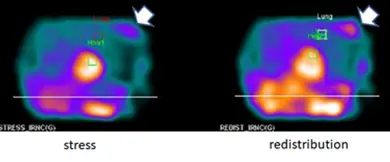

A壓力催迫( stress)後,肺部攝取量增加( lung uptake ),如附圖所示,可能代表嚴重且冠狀動脈多條血管阻塞

D在心臟以外區域若有 Thallium-201 同位素蓄積,如附圖箭頭所示,有可能是乳房腫瘤

- 選項A之附圖(Lung Uptake):在壓力(Stress)影像中,心臟周圍的肺部區域出現明顯的放射性攝取(Lung uptake),且心肌本身的背景對比度降低。這代表「肺/心比值」(Lung-to-Heart Ratio, LHR)上升。

- 選項D之附圖(Extracardiac Uptake):在心臟以外的胸部區域(如箭頭所示位置,通常為乳房區域)出現異常的放射性熱區(Hot spot)。